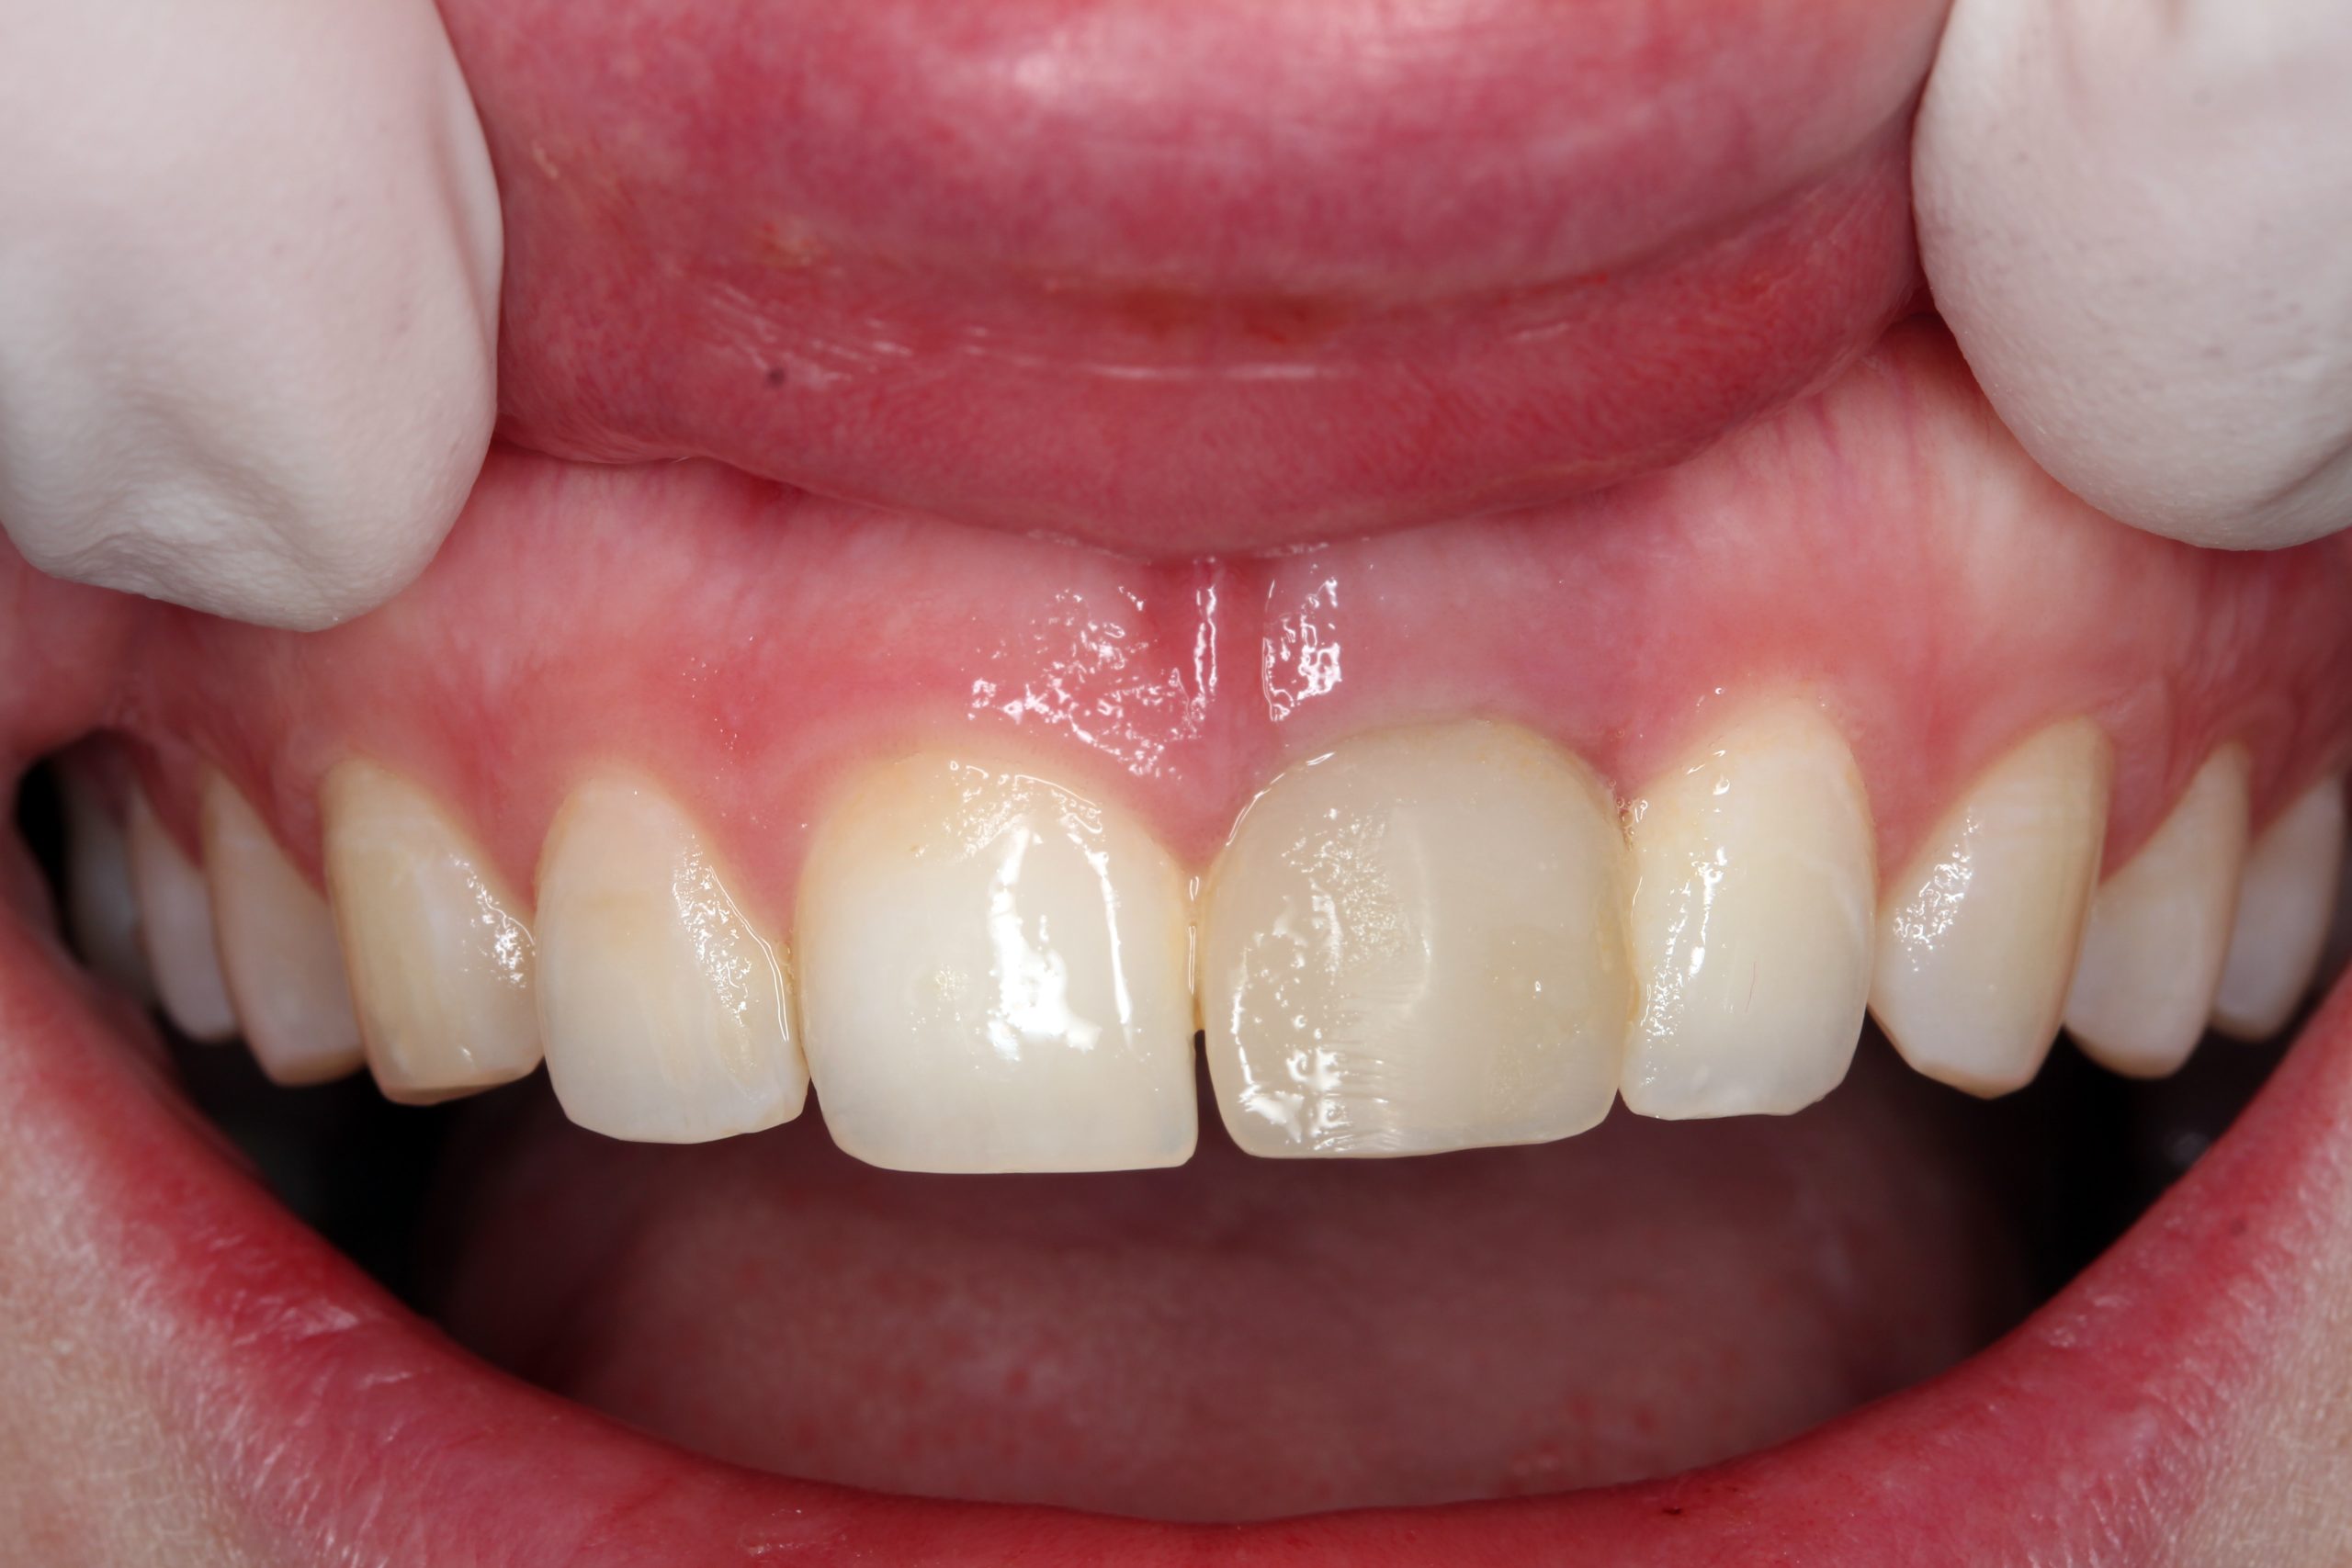

No problems occurred at the one-month follow-up. The temporary prosthesis was integrated into the surrounding tissue and the esthetics of the soft tissue were preserved.

Four months after implant placement and immediate loading, the temporary crown was removed. An all-ceramic crown was fabricated in the laboratory.